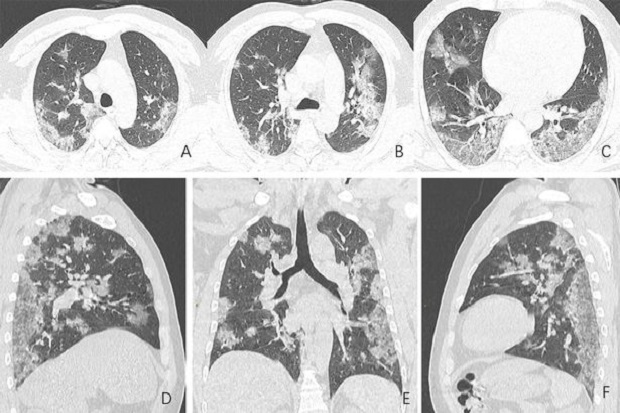

Eramuslim.com - CT scan dan rontgen paru-paru para pengidap virus corona baru, COVID-19, telah diambil setelah mereka ambruk dengan gejala demam dan...